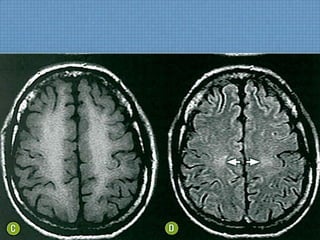

ACHADOS DE IMAGEM

• RM:

– Hipossinal em todas as sequências em

adenoipófise, determinada pela impregnação de

hemossiderina no local;

– Se acometimento de plexo corióide e meninges;

Pior prognóstico!

Abdomen: As alterações abdominais incluem

hipossinal em T2 e hiperdensidade à TC;

DIAGNÓSTICO

• Hemocromatose primária;

– Além dos achados típicos, é comum hiperssinal em

T1 nos núcleos da base, secundários à deposição

de Mn devido ao shunt portossistêmico;

– Acometimento pancreático  DM!

– Diagnóstico Fechado:

Clínica + Hipossinal em T1 com atrofia da

glândula